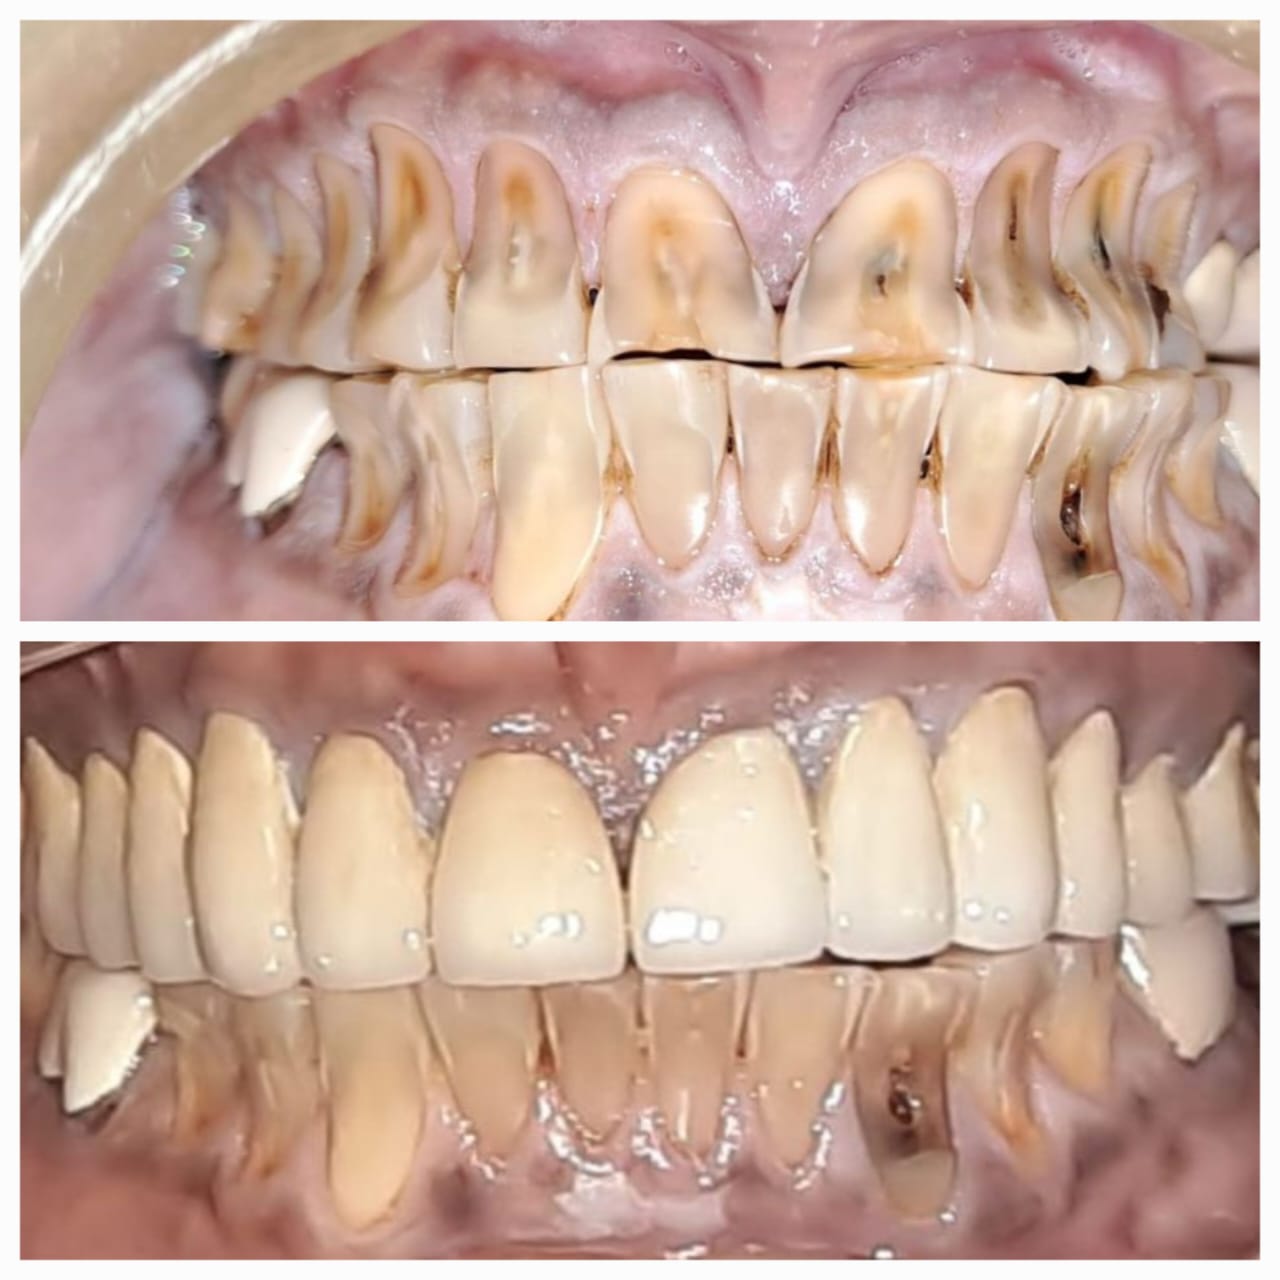

Case Scenario 2 - Full Mouth Rehabitilation

Exciting News! Discover the Steps of Full Mouth Rehabilitation for a Dazzling Smile! Are parafunctional habits like kharra and ghutka taking a toll on your dentition? Say goodbye to improper chewing, loss of facial aesthetics, and digestive troubles with our expert team at Chintamani Dental Clinic!

Step 1: Accurate Diagnosis Using our in-house OPG, we pinpoint the issues to create a tailored plan just for you.

Step 2: State-of-the-Art Treatments Experience top-notch root canal treatments and effective temporization protocols for optimal oral health.